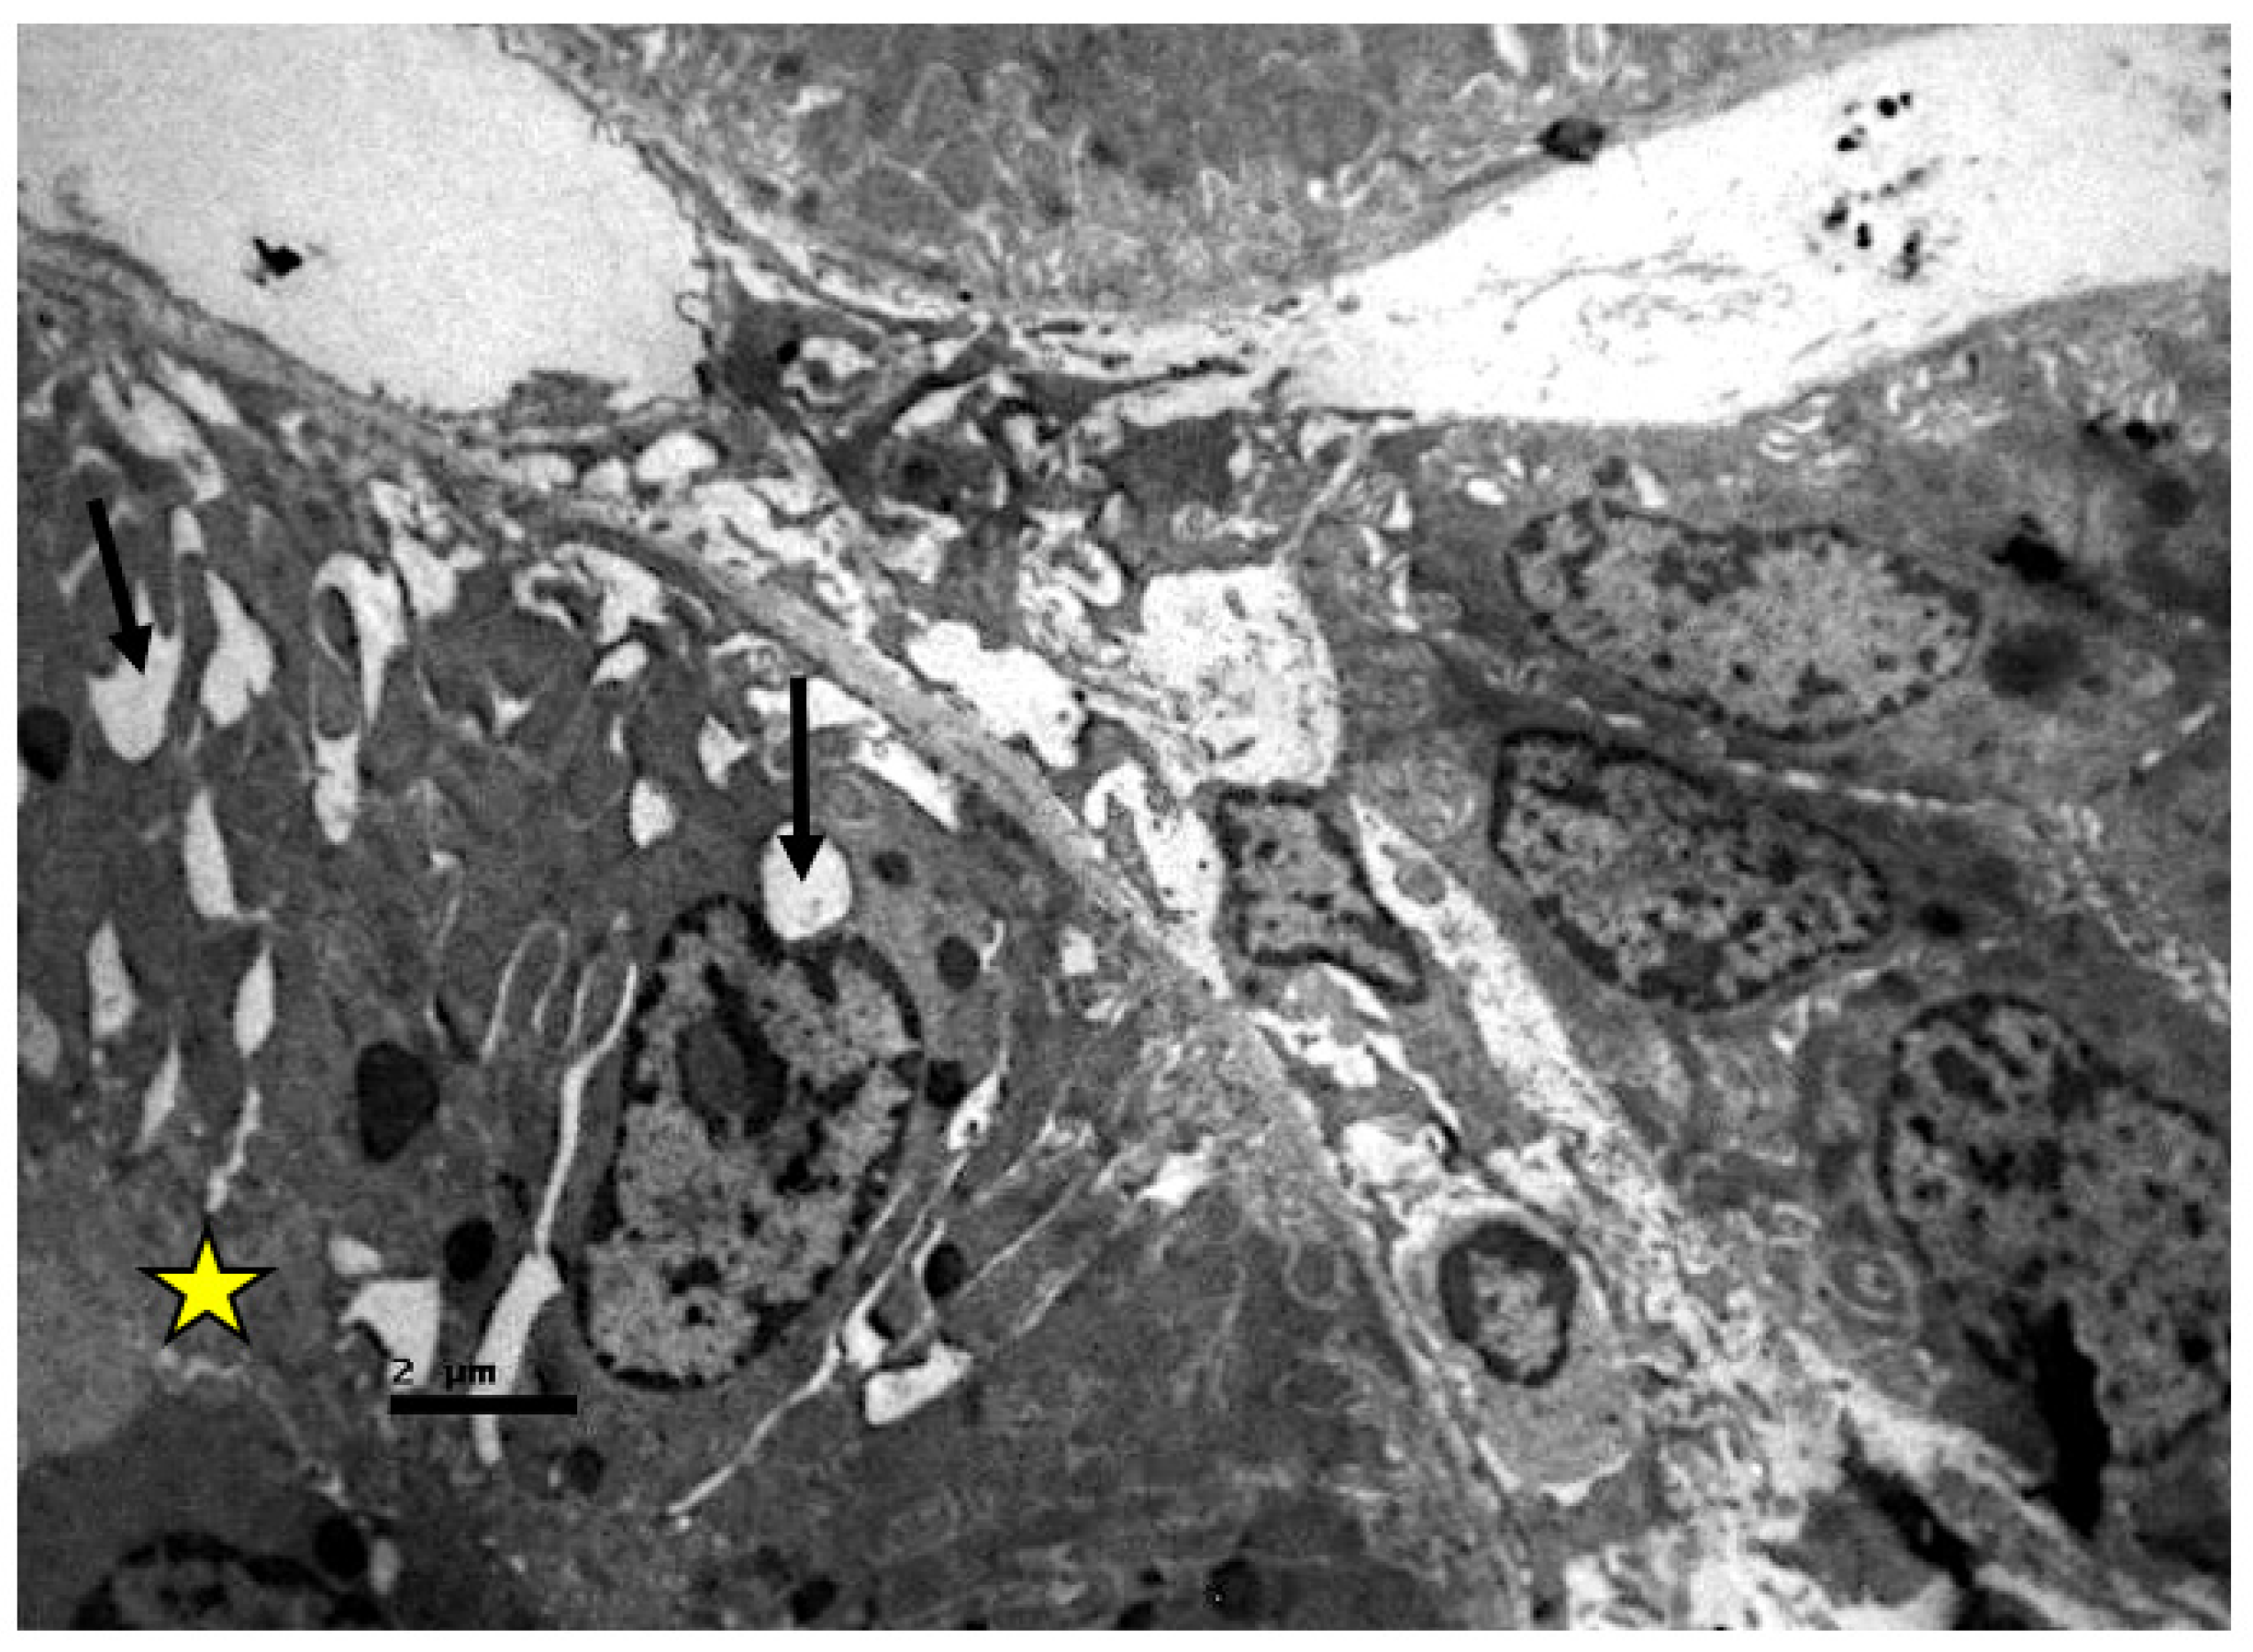

2.2. Electron Microscopic Evaluation